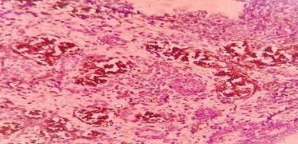

1) H&E 40X Reveals evidence of blastemal component <60%, immature tubular component, and cellular stroma.

Figure 3